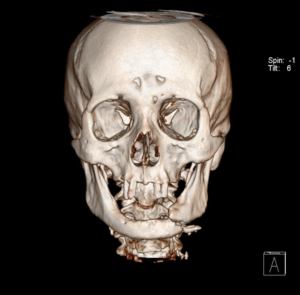

- Fraturas dos maxilares e órbita;

- Lesões craniofaciais (crânio, base do crânio e esqueleto facial);

O diagnóstico é feito pelo exame físico dos ferimentos e, nos casos de suspeita de fratura, deve se associar radiografias e tomografias computadorizadas. Esse avaliação poderá ser feita no hospital (se o paciente estiver internado) ou no consultório odontológico. O primeiro passo no tratamento é garantir a vida do paciente. O profissional deve garantir que o paciente esteja respirando bem e sem lesões graves que podem levar a morte rapidamente (como hemorragias severas, obstrução de vias aéreas e lesões de órgãos vitais)

A maioria dos ferimentos simples na pele pode ser tratada com anestesia local, limpeza da lesão e sutura. As fraturas da face e lesões complexas são tratadas sob anestesia geral. Os ossos quebrados são restaurados utilizando-se, geralmente, mini-placas e parafusos de titânio (que são biocompatíveis e não sofrem rejeição) que facilitam a recuperação e cicatrização óssea e dos tecidos